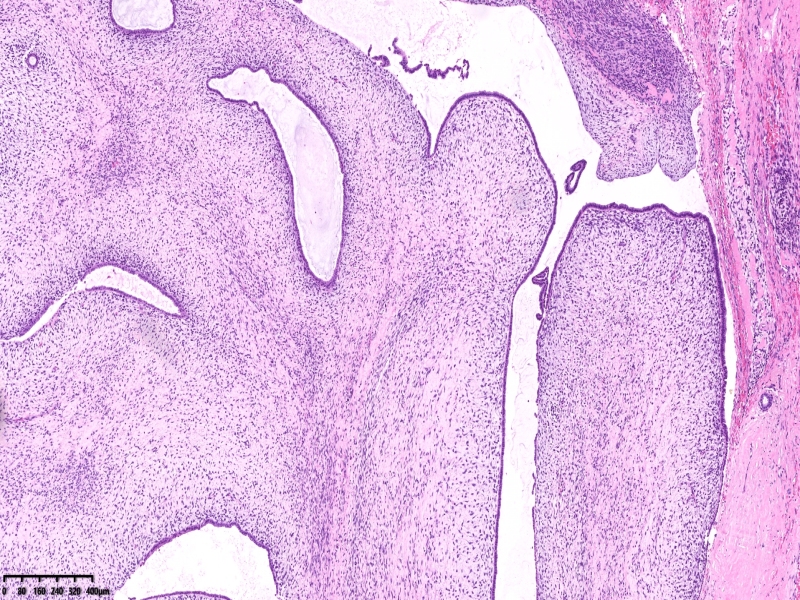

腺叶状肿瘤

2025-11-06 08:53 阅读(4) 评论(0) 分类:专业

患者女47,258081体积9*8*6厘米,目前遇到的最大的叶状肿瘤。